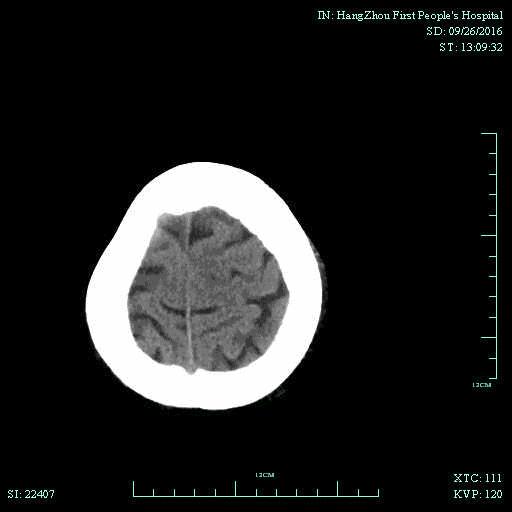

▼术后头颅CT复查:未见明显出血,左侧脑室旁可见少许低密度病灶。

术后第二天患者意识清,言语不清,右侧肌力恢复至3级,NIHSS评分2分,2周后右侧肌力5-级,NIHSS评分0分,行走出院。